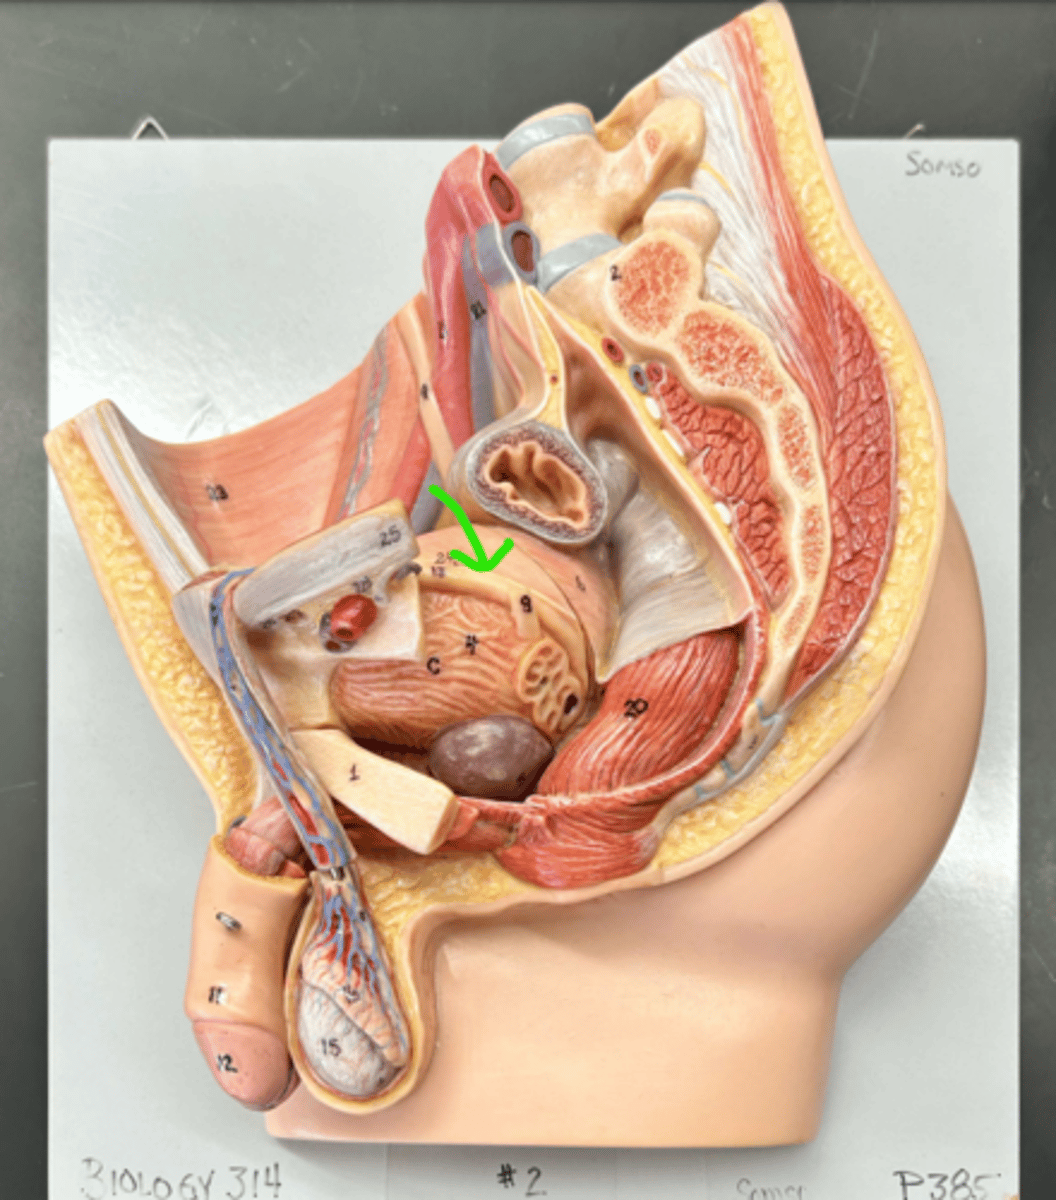

Epididymis

Epididymis

Head (epididymis)

Epididymis

Epididymis

Body (epididymis)

Tail (epididymis)

Spermatic cord

Ductus deferens

Ampulla (ductus deferens)

Ejaculatory duct

Seminal gland

Prostate gland